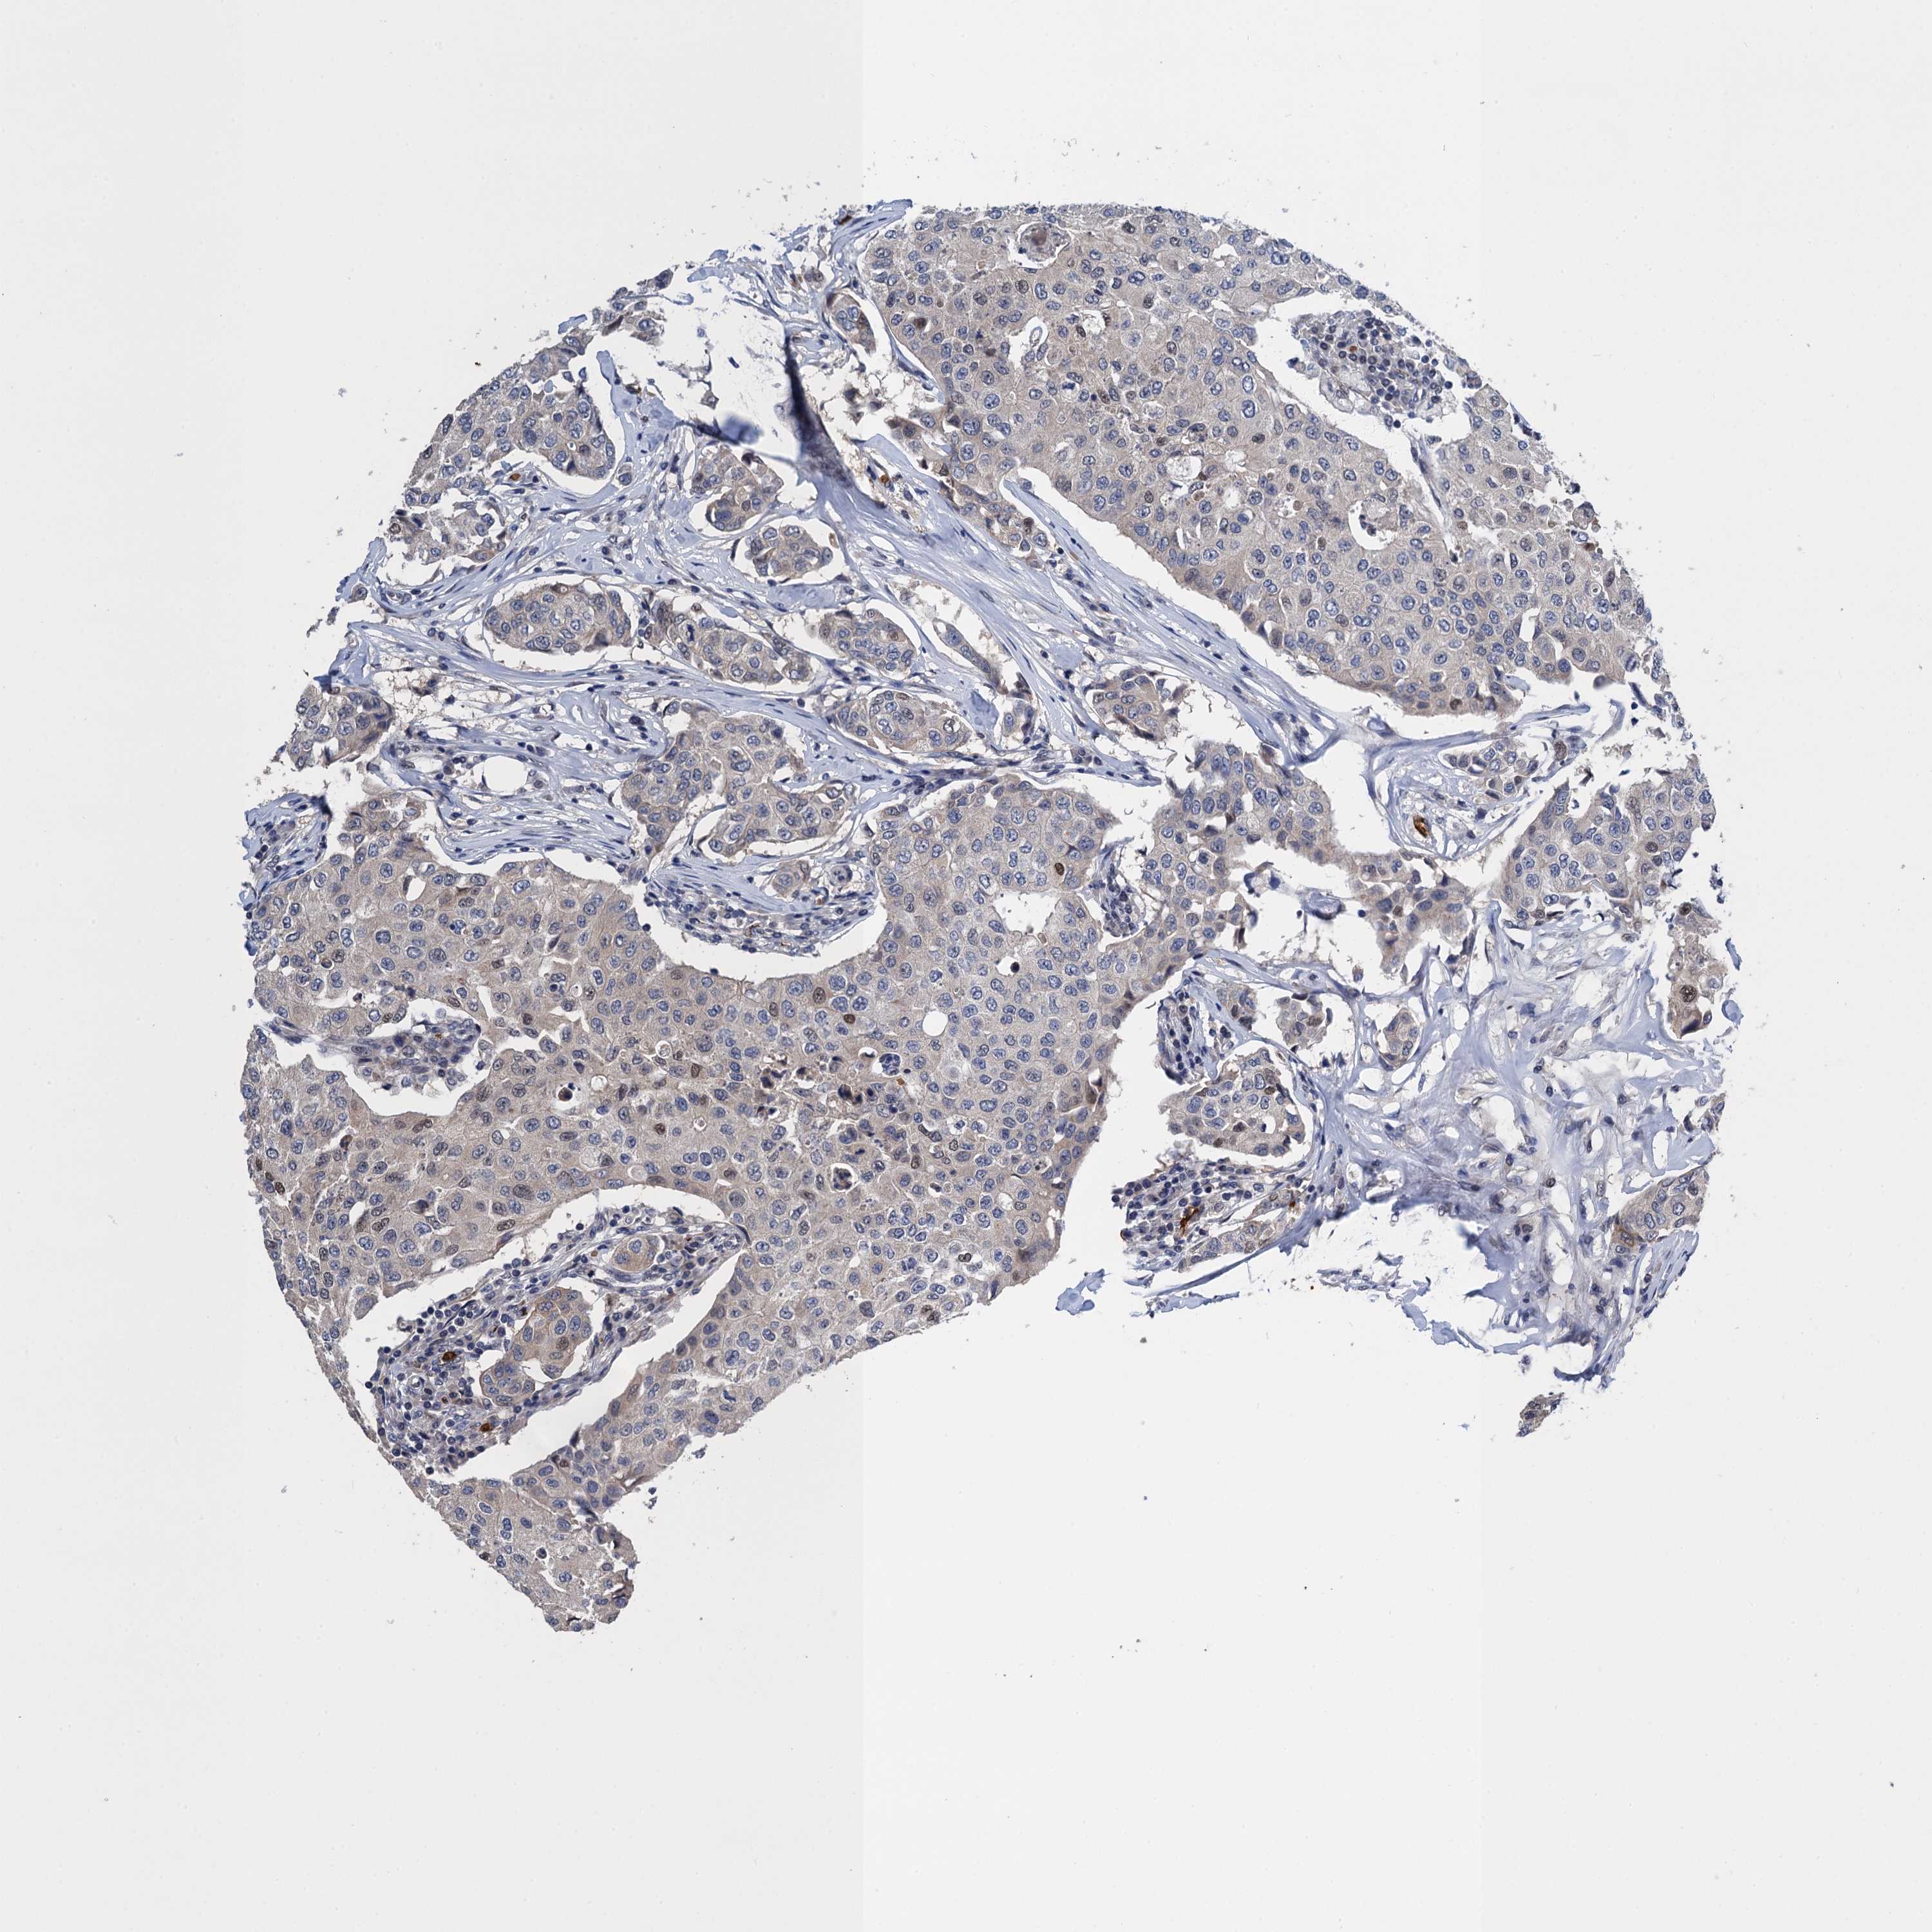

CANCER BREAST CANCER Show tissue menu

BRCA TCGA BRCA VALIDATION PROTEIN EXPRESSION

ANTIBODIES

AND

VALIDATION